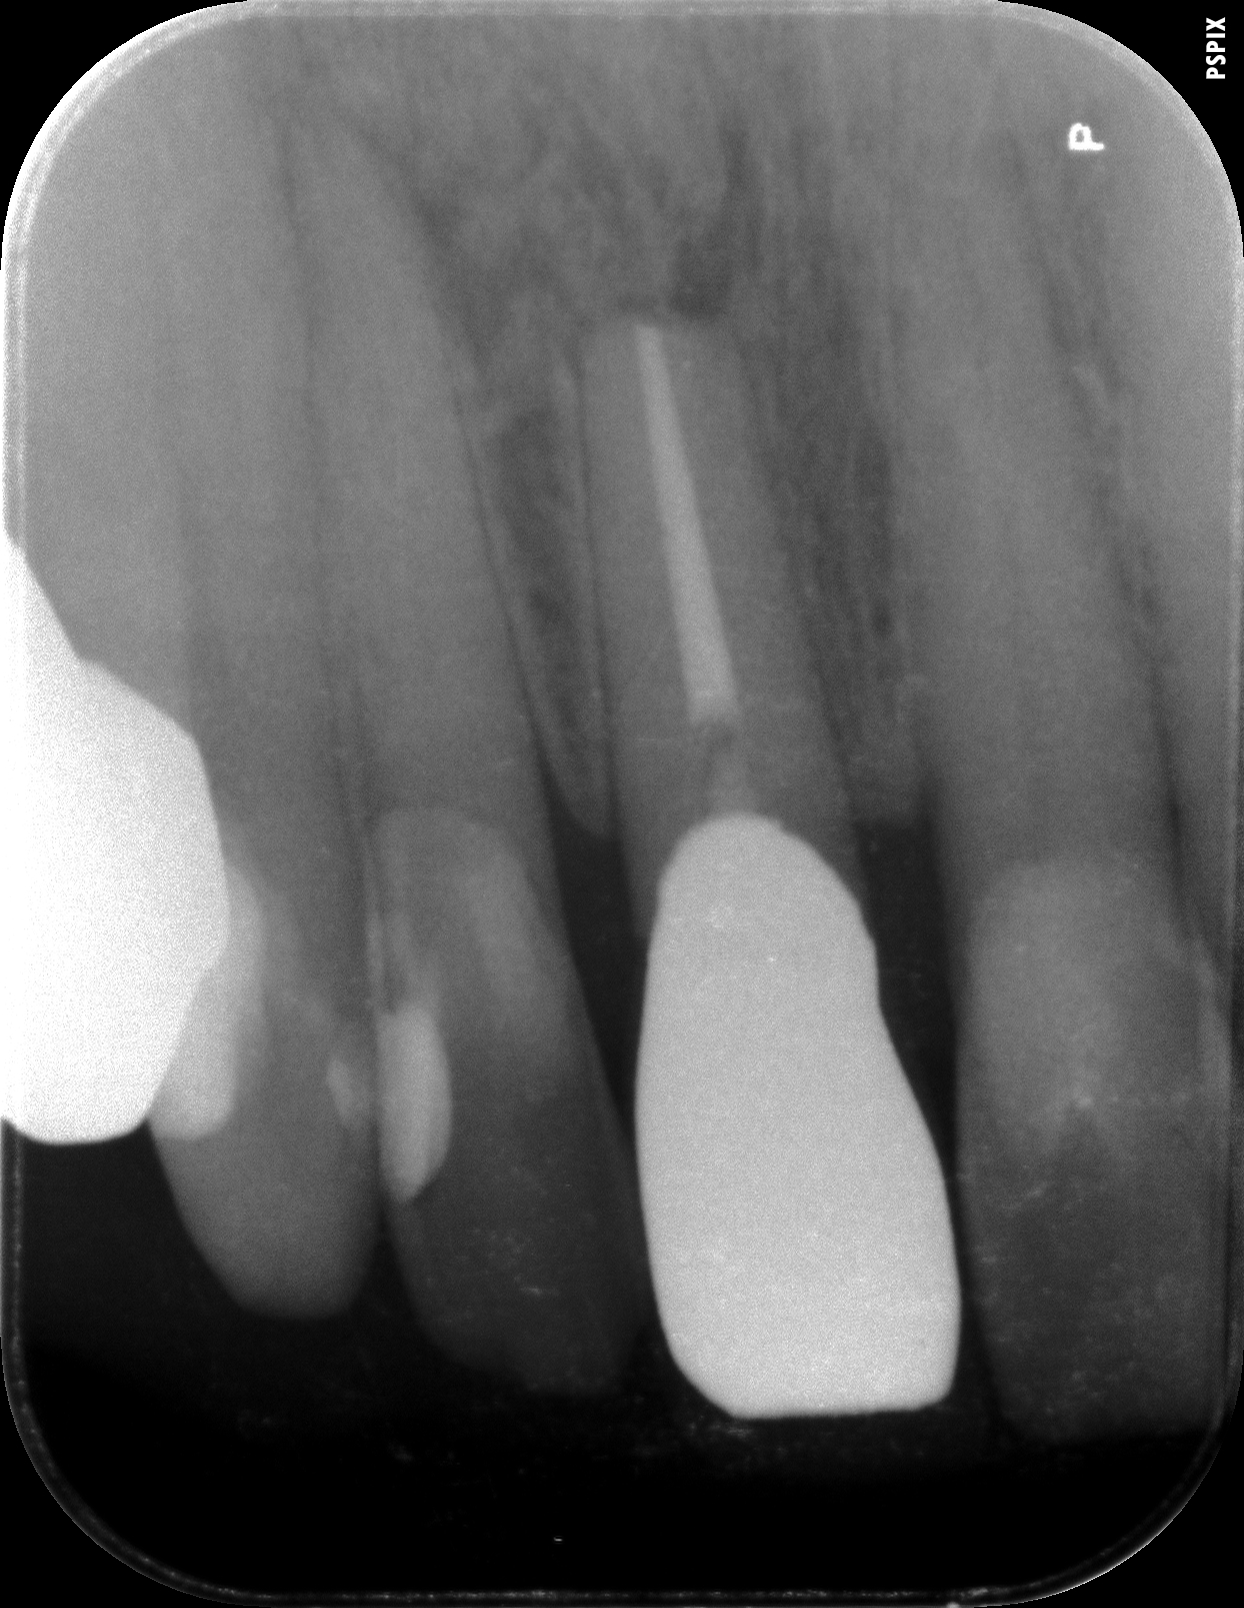

骨の欠損部は人工骨で満たされ黒い像が完全に消えています。